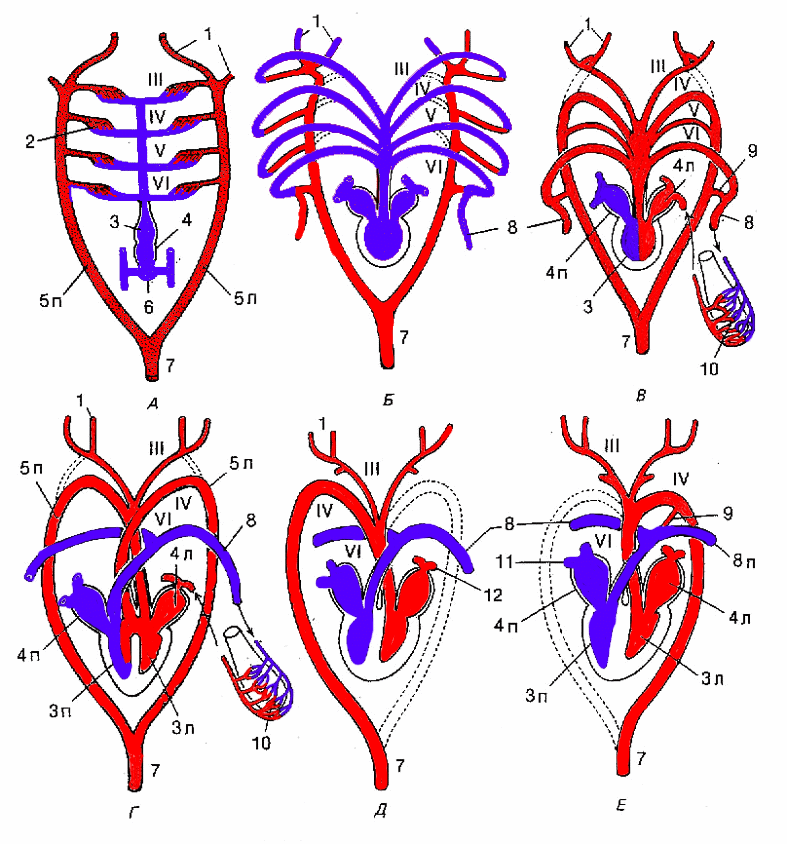

Кровеносная система человека: структура и функции